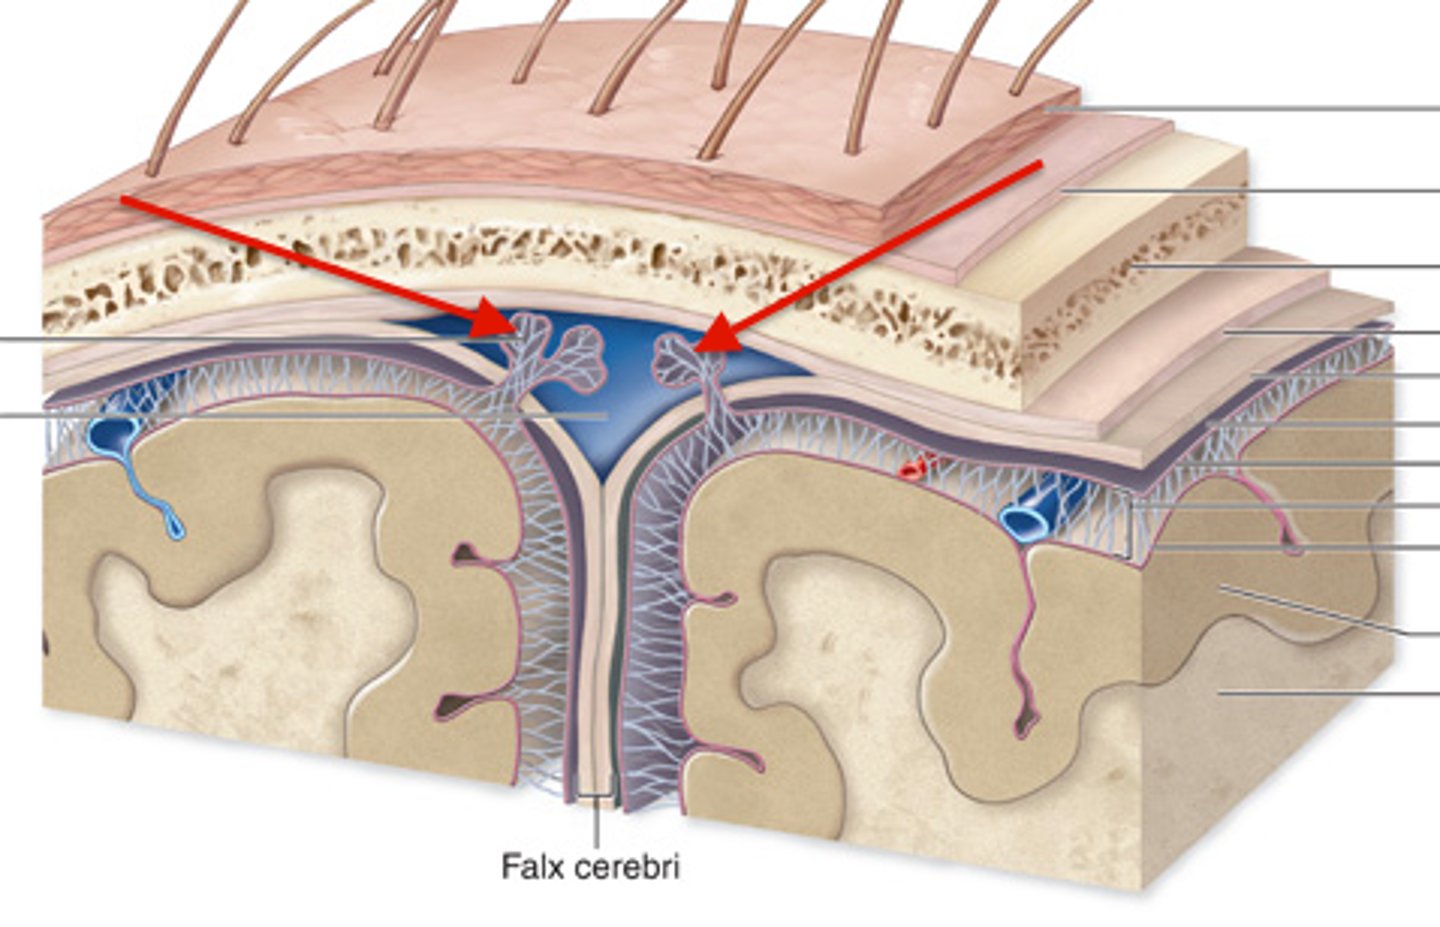

Dura mater

outermost layer of meninges - 2 layers, periosteal and meningeal

What is contained between the inner and outer layers of dura?

venous sinuses

what are the venous sinuses? where do they drain?

cerebrospinal fluid, they drain out of the internal jugular

superior sagittal sinus

inferior sagittal sinus

what are dural folds?

folded layers of dura where there is no sinus

falx cerebri

separates the two cerebral hemispheres

tentorium cerebelli

separates cerebrum from cerebellum

falx cerebelli

separates the two hemispheres of the cerebellum

arachnoid mater

middle layer of meninges, weblike

what is in the subarachnoid space?

cerebrospinal fluid

pia mater

"delicate mother," innermost layer of meninges

what attaches the pia mater to the surface of the brain?

collagen fibers

arachnoid villi

reabsorb/drain CSF into venous blood